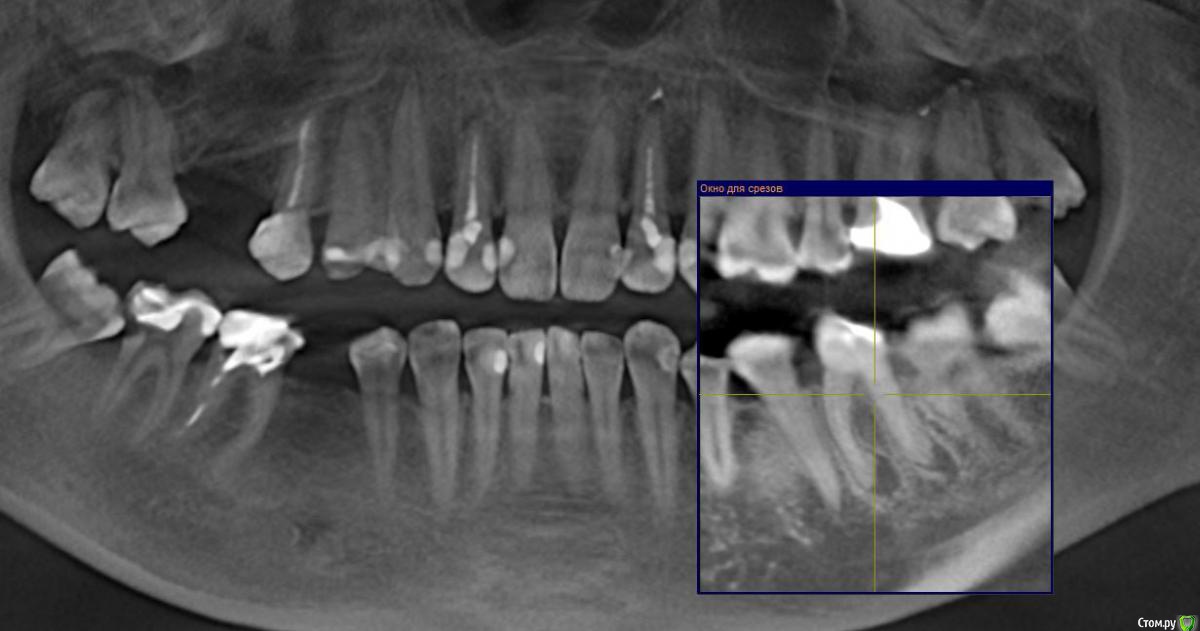

Gusenica Опубликовано 29 января, 2017 Поделиться Опубликовано 29 января, 2017 (изменено) Добрый день, уважаемые стоматологи! Прошу вас подтвердить правильность действия моих стоматологов. В частности интересует, безнадежен ли мой 36 зуб, на нем 2 кисты и я так и не поняла, почему их нельзя вылечить, но мой врач категорично настаивает на удалении. Зуб разрушен, имеет розово-серый цвет, лечился когда-то резорцином. На втором снимке киста на 22 зубе была обнаружена врачем уже после эстетического лечения, на ортопантомограмме она ее не увидела. А перелечивать мне не захотелось, при том она не настаивала, мол можно просто ее наблюдать, что она маленькая и неопасная. Так ли это? Может все же нужно лечить? И последний вопрос: зуб 46 -каналы пломбировались резорцином и сильно склерозированы. После консультации с ортопедом решили их не перелечивать, а сразу ставить на него коронку. Как вы считаете это правильное решение? Не появится ли там киста в итоге? Добавлю, что зубы с кистами никогда не беспокоили. Буду признательна за консультацию. Изменено 29 января, 2017 пользователем Gusenica Ссылка на комментарий

Доктор Добрых Дел Опубликовано 29 января, 2017 Поделиться Опубликовано 29 января, 2017 (изменено) Зуб 36 помимо кист (а точнее гранулём) имеет патологическую резорбцию корней в апикальной части поэтому перелечить его невозможно. Зуб 22 можно и наблюдать конечно, но канал недопломбирован, поэтому лучше перелечить. Зуб 46 кандидат на удаление так как судя по снимку разрушение копонковой части зуба потребует изготовления культевой вкладки, а так как каналы склерозированы их придётся рассверливать, а так как зуб резорциненый и хрупкий как стекло в будущем это с высокой ддолей вероятности приведёт к перелому корня. Я бы рекомендовал удаление 36, 46 и установку имплантатов. Перелечтвание 22. Прошу учесть, что рекомендации не являются руководством к действию. Решение принимать Вам и Вашему лечащему врачу. Изменено 29 января, 2017 пользователем Доктор Добрых Дел 1 Ссылка на комментарий

DrNice Опубликовано 30 января, 2017 Поделиться Опубликовано 30 января, 2017 Соглашусь с постом выше, кроме 46 зуба, за него я бы поборолся. Адекватное перелечивание, культевая вкладка и коронка. Да риски есть, в любом случае решение принимать вам и вашему лечащему врачу.P.S. Имплантация более прогнозируемый вариант Ссылка на комментарий

Gusenica Опубликовано 30 января, 2017 Автор Поделиться Опубликовано 30 января, 2017 Спасибо большое за ответы. Восьмерки уже удалили нижние, верхние не мешают вроде. Мой стоматолог не собирается перелечивать каналы 46 зуба, отправила меня сразу к ортопеду ставить коронку. Может все-таки настоять на перелечивании или можно и так коронку ставить? Да, там еще и штифт стоит. Меня это немного настораживает, не будет ли потом осложнений, если каналы не трогать? Ссылка на комментарий

inSight Опубликовано 12 февраля, 2017 Поделиться Опубликовано 12 февраля, 2017 Может все-таки настоять на перелечивании или можно и так коронку ставить? Да, там еще и штифт стоит. Меня это немного настораживает, не будет ли потом осложнений, если каналы не трогать?Есть риски, Док их оценил, ортопедия. Осложнения будут - если вовремя ничего не трогать. Ссылка на комментарий